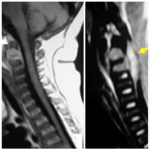

INSTRUCCIÓN ORTOPÉDICA DE POSGRADO – IMÁGENES

Presentación del caso

Pedro L. Bazán, Arles Pérez Gutiérrez, Alin L. Garay

Resolución del caso